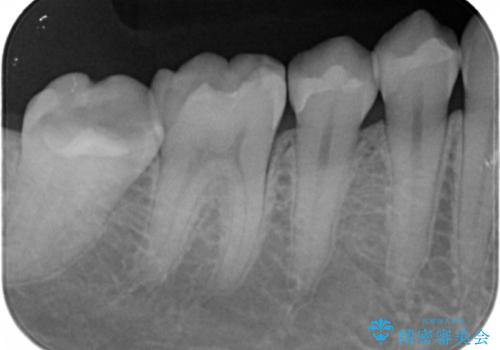

今回は虫歯の治療のみのご希望であったため、掲載している写真の右側2本(口腔内の手前側)を治療していきました。

写真の左側2本(口腔内の奥側)は適合が悪いことが見て取れると思います。

こういった場所は汚れがたまりやすく虫歯のリスクが高くなっているため、適合の良い修復物にやりかえることをお勧めします。